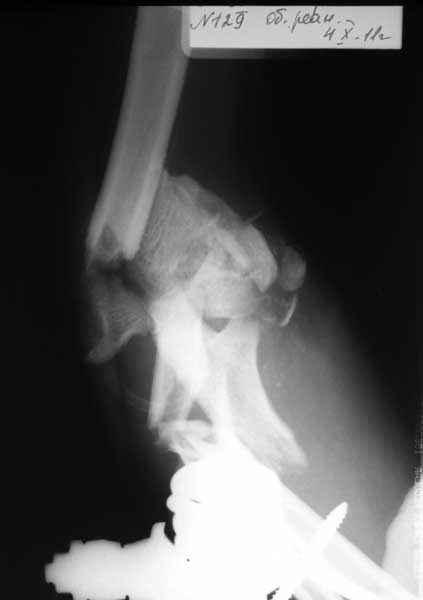

Выкладываю изображения.

План лечения: открытая репозиция. Собрать суставные фрагмент. Фиксация: спицы, кан.шурупы, реконструктивные пластины, АВФ с локтевым шарниром. Бусы с ванкомицином. Дренирование, вакууимирование.

КТ - вот это другое дело!

естествено - репозиция отломков плеча, однако, не заморачивайтесь с суставом...